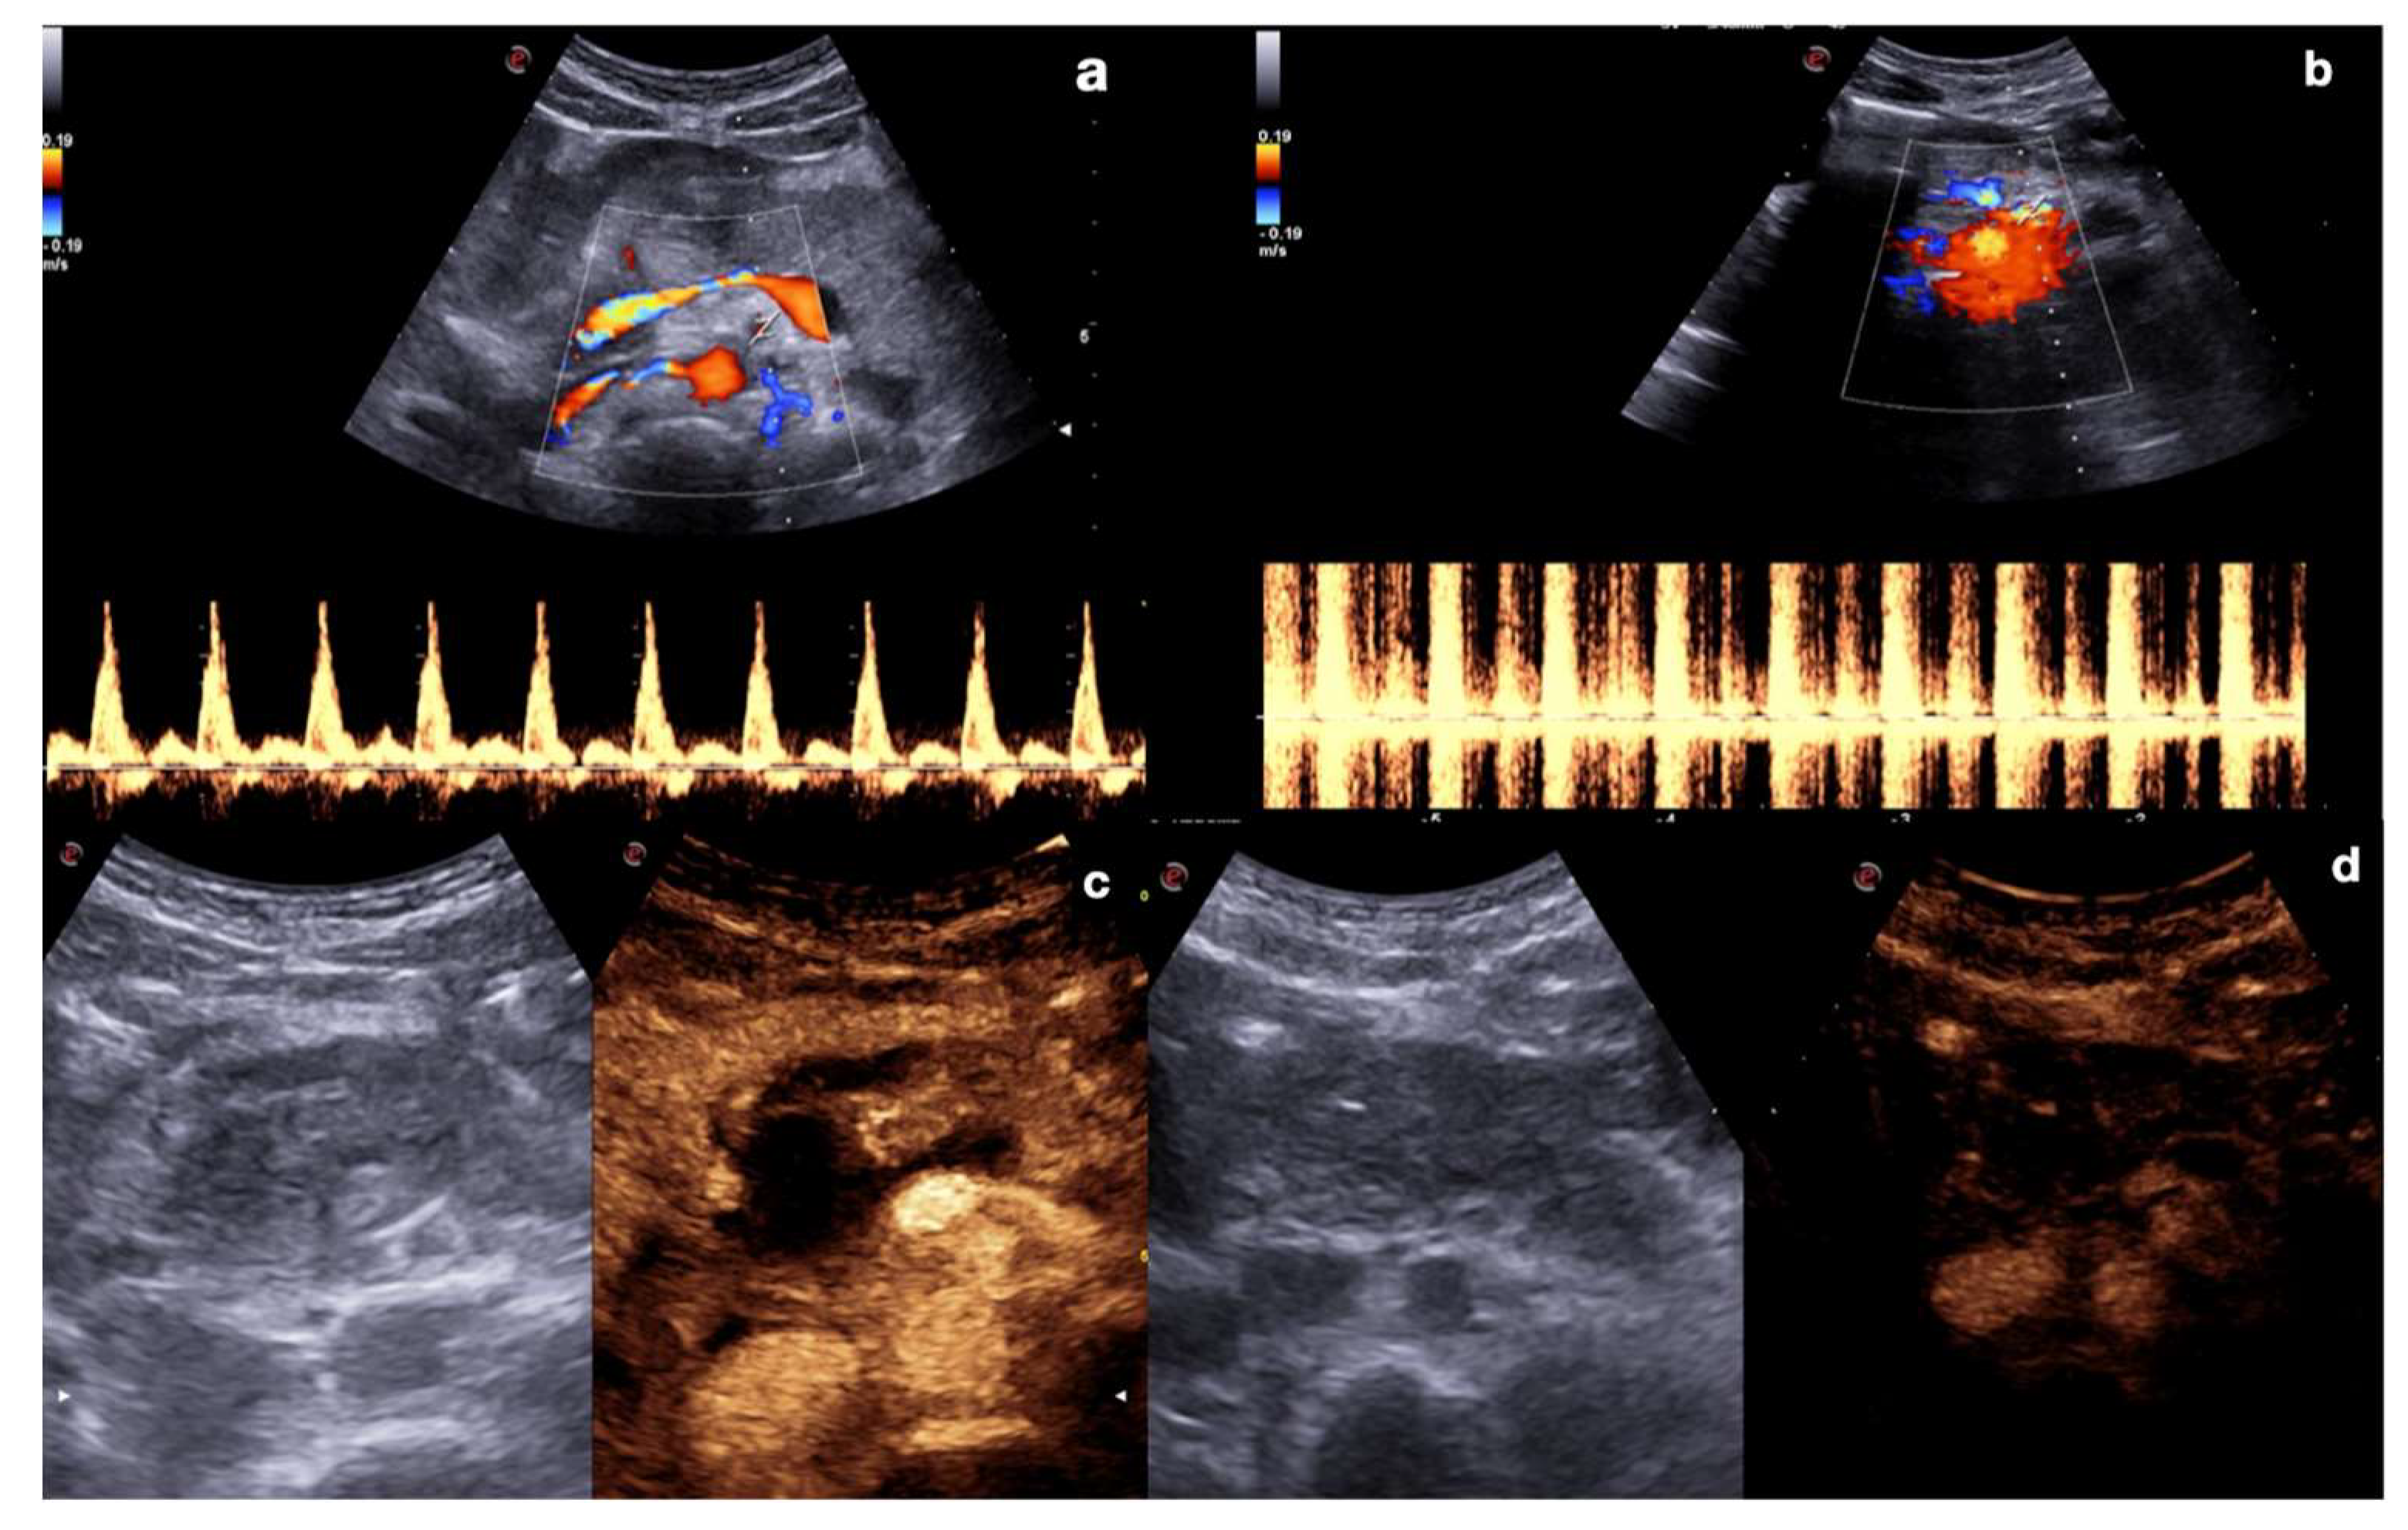

2.3.2. Vascular Injuries

- Active bleeding:

- Contained vascular injuries:

| 10–20 s (early) 20–40 s (late) | Arterial phase: best depiction of contained vascular injuries, such as pseudoaneurysms and arteriovenous fistulas in the early phase. |

| 2–6 min | Venous-late phases: distribution of the contrast in the whole organ. Best time to depict parenchymal injuries. |